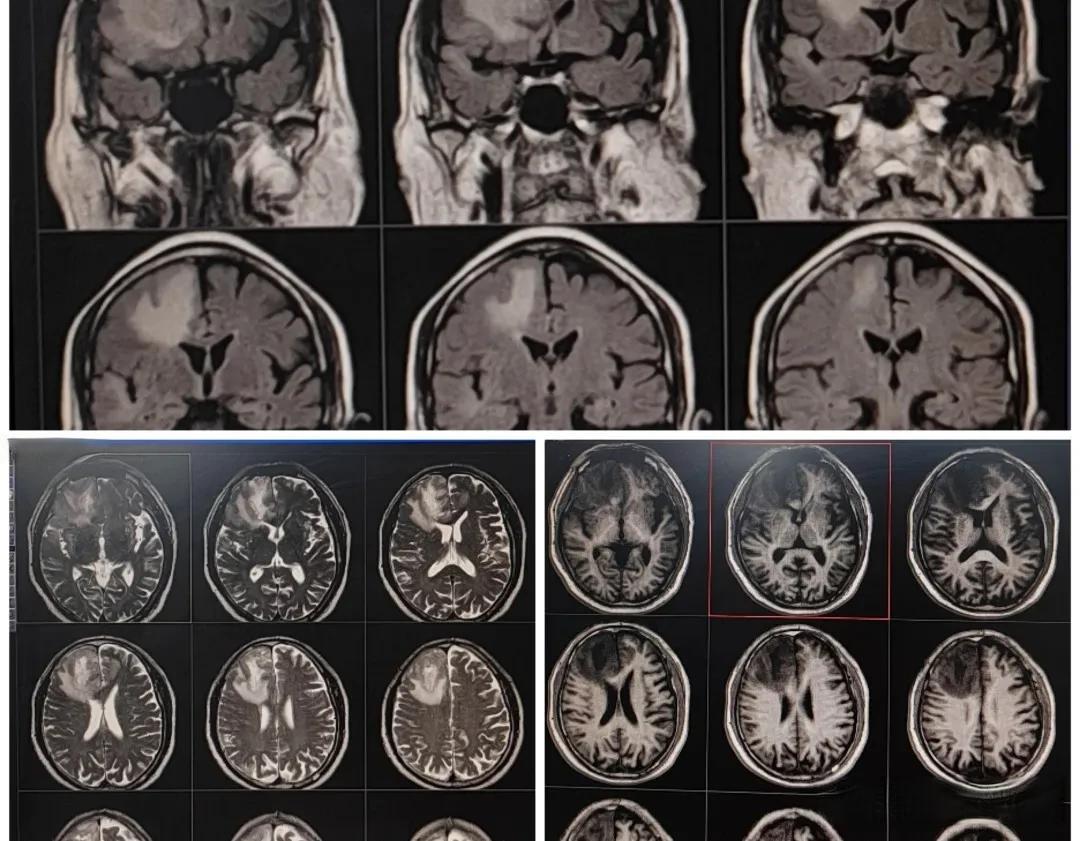

诊断方法上,脑肿瘤通常需要通过MRI或CT扫描来确认。而脑梗死则可以通过CT扫描、MRI或血管造影来诊断。值得注意的是,早期诊断对两种疾病都至关重要。对于脑肿瘤,早期发现可以提高治疗成功率;对于脑梗死,时间就是大脑,越早治疗,越能减少脑损伤。